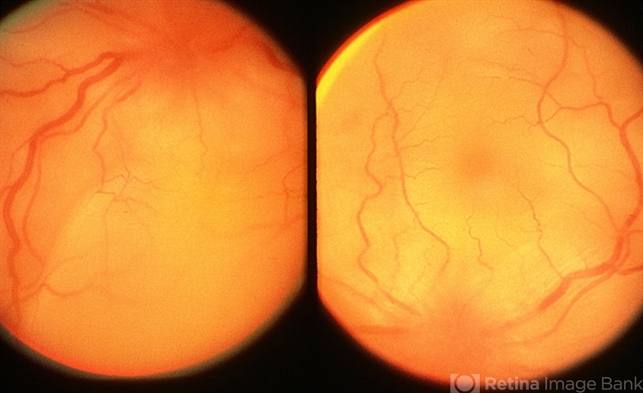

- VKH acute stage; bilateral multiple serous detachments in the same patient with vitiligo and poliosis.